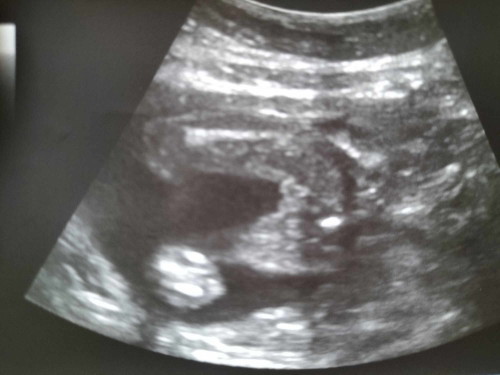

แม่ๆดูออกไหมค่ะว่าน้องเป็น ช/ญ ค่ะ เราท้องได้ 21 สัปดาห์ค่ะ ในสมุดคือสิ่งที่หมอเขียน แต่ไม่บอกเรา แม่ๆช่วยดูให้หน่อยได้ไหมค่ะ 🥰🥰 ลุ้นมาก อยากรู้ๆ#ขอบคุณล่วงหน้าสำหรับความคิดเห็นค่ะ

หญิงนะแม่ ของเราลูกชายเห็นตั้งแต่14วีคจะมีจรวดพุ่งแหลมๆอยู่ตรงกลางเลยทั้ง2คน 21วีคค่อนข้างชัดแล้ว แต่ใดๆก็สามารถหลบได้เหมือนกัน

ภาพอัลตร้าซาวด์เหมือนบ้านนี้เลยค่ะคุณหมอบอกว่าน่าจะเป็นผู้ชายแต่ยังไม่ชัวร์ ซาวด์ตอน20วีค ตอนนี้28แล้วยังไม่ได้ซาวด์อีกเลย😂

น่าจะผู้หญิงนะคะ คนแรกแบบนี้ออกมาก็ผู้หญิง ส่วนท้องนี้ได้ผู้ชาย โด่งนำมาเลยค่ะ

น่าจะ ผญ. ถ้า ผช. จู๋คงโด่เหมือนลูกเรา เพราะท่าเดียวกับลูกชายเลย

ผู้หญิงค่ะแม่เพราะเราลูกชายจู๋น้องจะโผล่มาชัดเลยไม่เป็นแบบนี้ค่ะ

ลูกสาวค่ะ ของบ้านนี้ก็แบบนี้เลยป้าหมอแซวว่า2กีบชัดเลยนะ🤣🤣

น่าจะ ผญ นะคะ เค้าซาวตอน20วีคค จู๋น้องโผล่ออกเลยค่ะ

ผู้หญิงค่ะของเราก็แบบนี้เลยค่ะหมอบอกว่าผู้หญิง

ชัดเจน ญ ค่ะ ไม่มีจู๋ เด่ขึ้นมา ยินดีด้วยนะค่ะ